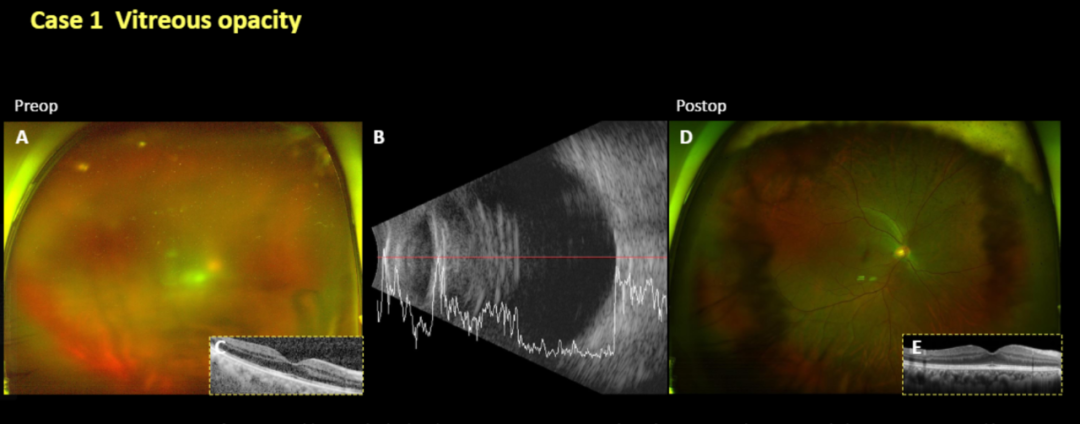

病例1

一例50岁男性患者,4个月前接受右眼白内障手术,术前表现为玻璃体混浊,视力为logMAR 1.0(A)。超声图像显示玻璃体混浊伴视网膜平伏(B)。SD-OCT扫描显示黄斑完整。进行玻璃体切除以去除混浊玻璃体,并获得玻璃体样本进行细菌和真菌培养。玻璃体检查未发现任何感染的迹象,葡萄膜炎似乎是特发性的。术后1年6个月眼底图像显示眼底和黄斑清晰完整(D,E),最终视力为logMAR 0.0。